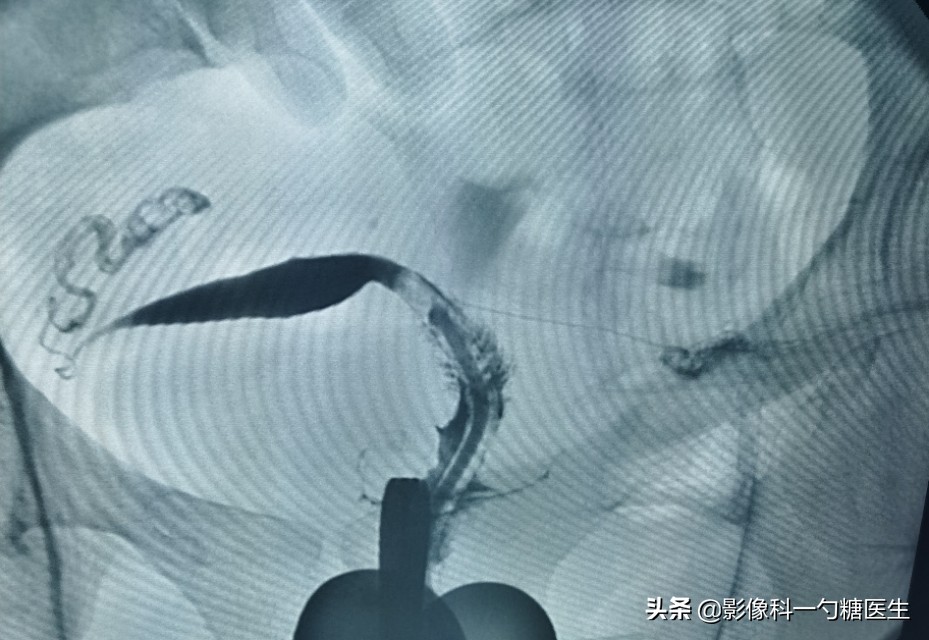

女,34岁,一年前宫外孕术后,至今未孕,生育史:G1P0,偶尔月经不准时。晚婚的小余在婚后的第四个月就怀孕了,但却没有第一时间去医院检查,以至于最后发现宫外孕时,不得不手术治疗。

小余是上周来检查的病人之一,但只有她一个的检查结果是异常的,因为只剩一侧输卵管了(下图④)。

图④:小余的造影图

异位妊娠 即“宫外孕”,受精卵在子宫腔以外的部位着床、发育。最常见的部分为输卵管。

输卵管的妊娠不及时治疗可造成破裂、出血、休克等。而输卵管妊娠发生的常见因素:

- 输卵管本身异常,炎症、盆腔术后粘连、肿瘤压迫牵拉等。

- 受精卵的异常游走,发育增大后而种植在输卵管内。

- 避孕失败,宫内节育器避孕失败后,并发输卵管妊娠的几率增大。

而只剩一侧输卵管的患者,怀孕几率本身就只剩50%了,如果对侧的输卵管堵塞不通,那自然受孕的几率几乎为零。

而切除了左侧输卵管的小余,右侧的输卵管虽然通畅,却也有少量积水,所以一直再难受孕。